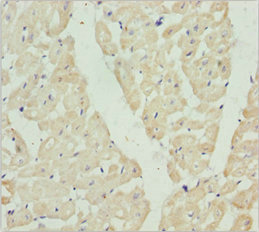

Immunohistochemistry of paraffin-embedded human heart tissue using CSB-PA614992ESR2HU at dilution of 1:100